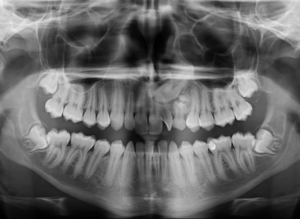

Por lo cual se diseñó un estudio transversal con 74 contactos de 28 imágenes CBCT existentes de niños de entre 3 y 14 años, obtenidos de la Academia de Educación Dental de la India, Chennai, India. La forma del área de contacto se observó en tres niveles, los tercios coronal, medio y apical, en tres secciones diferentes de CBCT. La prevalencia de los tipos de áreas de contacto se expresó en forma de números y porcentajes. Los resultados mostraron cuatro tipos diferentes de áreas de contacto entre los molares primarios, a saber, tipo O, tipo X, tipo I y tipo S, según las formas observadas; Por lo tanto, la clasificación propuesta se conoce como OXIS. El patrón más común observado fue I (66.2%), seguido de X (21.6%), O (9.4%) y el menos común fue S (2.7%). (Figura 1 y Figura 2)

Llegando a la conclusión que la evaluación tridimensional de las áreas intactas de contacto interproximal entre los molares primarios es de cuatro tipos, O, X, I y S.